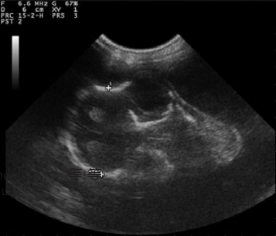

羊用B超机对双顶径(BPD)的测定

BPD的超声测量是常规的在产前检查和估计期间进行各种山羊品种中的GA含量,测量的标准BPD如下:尽可能椭圆形,封闭头骨表轮廓,大脑中线分裂克将半球分成两个等距的部分并测量-取自近端的外表面颅骨到远端颅骨内表面。头部扫描应在轴向平面上进行。图像对称性对于准确测量至关重要。很高相关性之间妊娠中期GA和BPD已经升高,BPD是也很难之后测量胎儿出生后第95天胎儿其他部位压迫头部,和也的变化性的胎儿的位置和姿势。因此,据报道,相关系数较低第60至135天之间的韩国黑山羊妊娠。

图4超声图像上的双顶径胎儿在妊娠70天